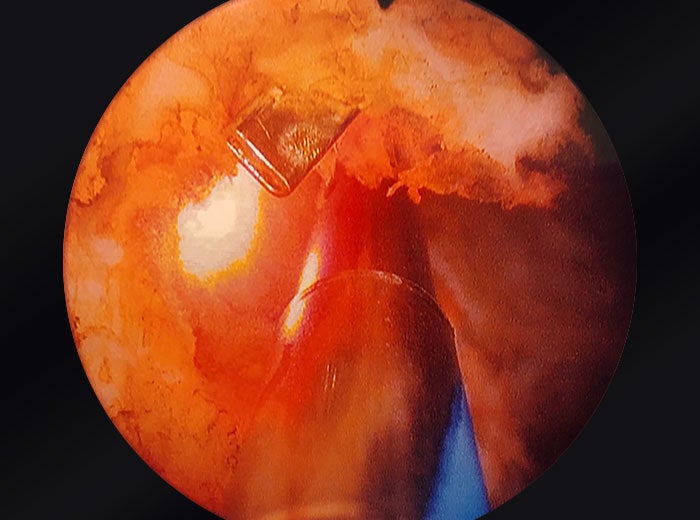

UroLift clips embedded in prostatic tissue

Images provided courtesy of Dr. Ricardo Gonzalez.

OR camera zoomed into prostate.

Tissue extracted from a Urolift procedure.

And at the end of the procedure, I confirm that there is no foreign bodies that are visible, and make sure that any tissue that needs to be removed is removed. And I get hemostasis using the same laser.